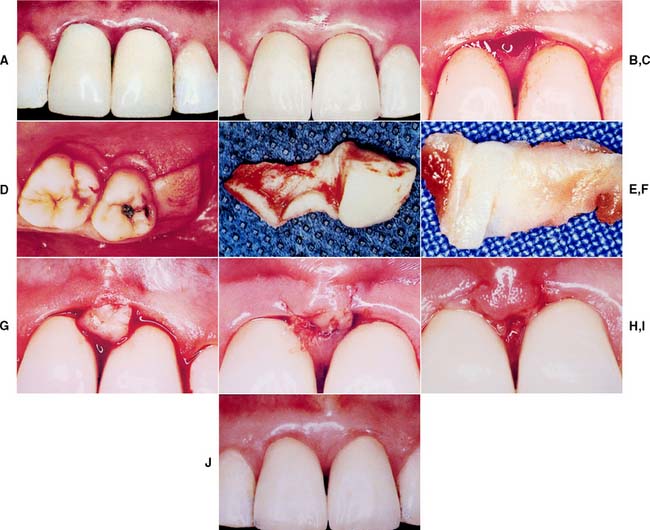

Surgical crown lengthening or extension (Fig. 6-16) may be indicated to improve the appearance of an anterior tooth or when the clinical crown is too short to provide adequate retention without the restoration’s impinging on the normal soft tissue attachment61 or biologic width.* This attachment averages approximately 2 mm in width, and any restoration that impinges on it may cause bone loss because of the effort of the host to maintain the 2 mm distance. If impingement occurs in an interproximal area, it can lead to problems with plaque control and possible osseous resorption.62-64 Therefore, from the standpoint of prognosis, the biologic width should never be compromised.

Fig. 6-16 Surgical crown lengthening. A, Fractured and carious second premolar. B, Reflection of a flap and removal of granulation tissue. C, Bone removed on the mesial aspect to increase the distance to the fracture site to 3.5 mm. D, Distally the bone is removed so that there will be 3.5 mm from the caries to the alveolar crest. E, Healing after the surgical crown lengthening. F, Final crown restoration after cementation, before restoration of the sextant with a removable dental prosthesis.

In some patients, an apparently unsalvageable tooth with extensive subgingival caries, a subgingival fracture, or root perforation resulting from endodontics can be successfully restored after crown lengthening. Crown lengthening increases the crown/root ratio, however, and a pretreatment decision must be made about whether the tooth should be removed or restored.

Crown lengthening may be accomplished either surgically or with combined orthodontic-periodontic65-69 techniques, depending on the patient and the dental situation.

It is sometimes possible to achieve an effective increase in crown length by gingivectomy or removal of gingiva by electrosurgery alone (see Fig. 6-16), although osseous recontouring is most often needed to prevent encroachment of the prosthesis on the biologic width. For these procedures, a full-thickness mucoperiosteal flap is reflected, and the osseous resection creates 3.5 to 4.0 mm of space between the gingival crest and the margin of the existing restoration or carious lesion.61,70 In these instances, however, the following factors should be considered:

Restoration of a tooth that has undergone crown lengthening is commonly undergone in 4 to 6 weeks after the surgical procedure. A clinicale study73 has demonstrated that the biologic width and the position of the free margin of the gingivae exhibited no change at 3 to 6 months after surgery. Therefore, it may be advisable to provisionally restore that tooth in question, either before or immediately after surgical crown lengthening, and subsequently fabricate the final restoration after 3 months.